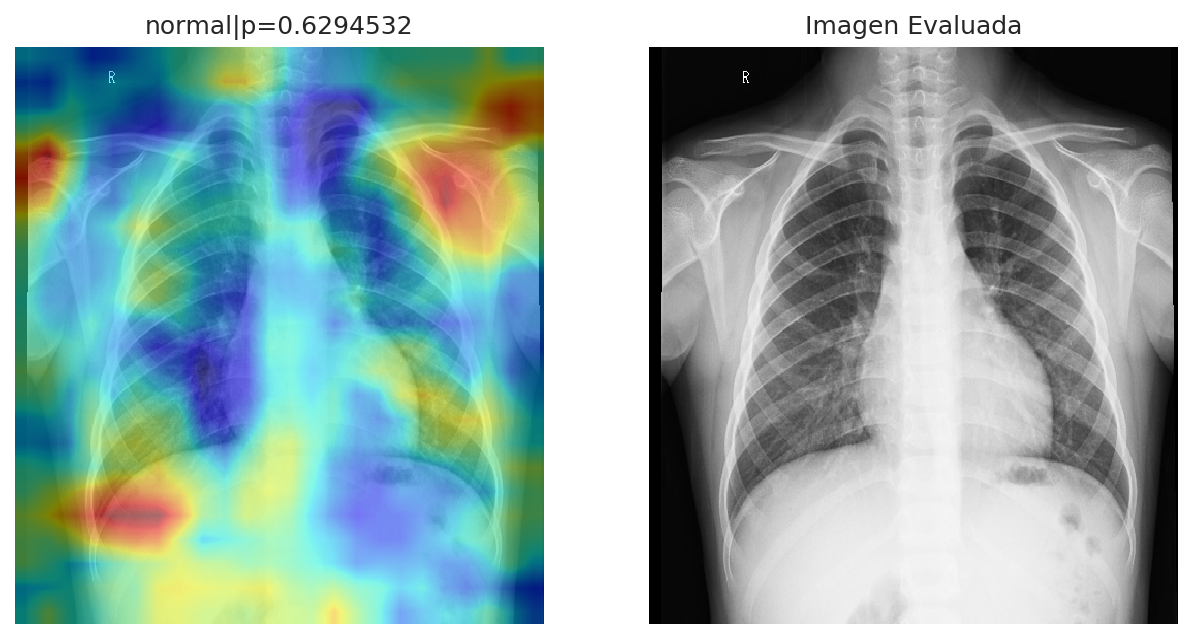

The diagnosis discards the presence of pneumonia in the patient. From the analysis, the patient present a normal state, with a 62.95% of confidence. Whereas the probability of having pneumonia is: 37.05%. The distribution for both states can be observed in the plot.

Diagnosis Summary: The patient do not show signs of having pneumonia.

The zonal analysis shown, which areas from the image, where used to carry on the diagnosis. This represent the zones where the algorithm detect pneumonia or a normal state. The cold colors, represent the zones, which have a probability of having a normal state, whereas the warm colors represent the probability of pneumonia in such zones. This information is intended to bring support as evidence about the diagnosis. Since this application is under development, some zones mark areas out of the main image. This will be improved in the next iterations. To see the analysis in more detail, click on the image to zoom in.